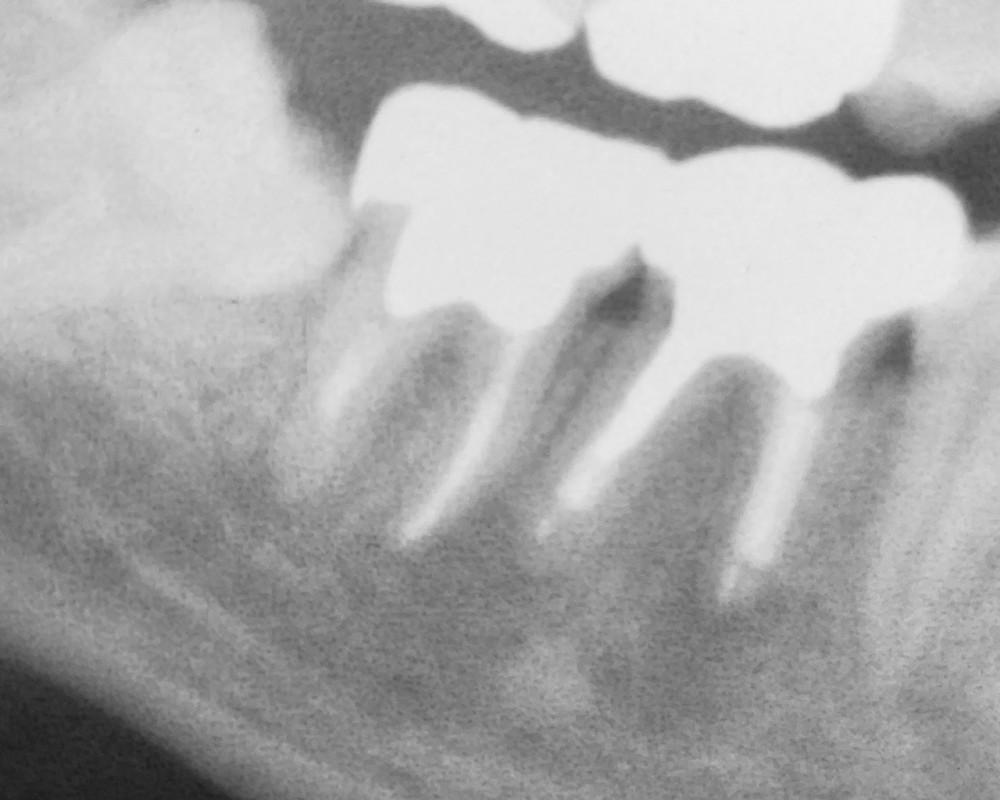

上のエックス線写真は、20代男性、初診時(令和4年12月)のものです。

右下奥歯の痛みを訴え、来院されました。

前医では、おそらく生活歯髄切断という治療を行ったものと推測されます。

下の図の黄緑色の丸いラインで囲まれた部分に、(右下奥歯の歯根の先端部分の歯槽骨内に)炎症が疑われます。